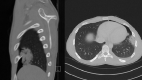

Non-traumatic complications of a solitary rib osteochondroma; an unusual cause of hemoptysis and pneumothorax

Osteochondromas are a very common and usually asymptomatic entity which may originate anywhere in the appendicular and axial skeleton. However, the ribs are a rare site of origin and here they may prove symptomatic for mechanical reasons. In this case report, we describe an unusual case of a symptomatic osteochondroma of the rib secondary to its location and unique shape, ultimately requiring surgical intervention.